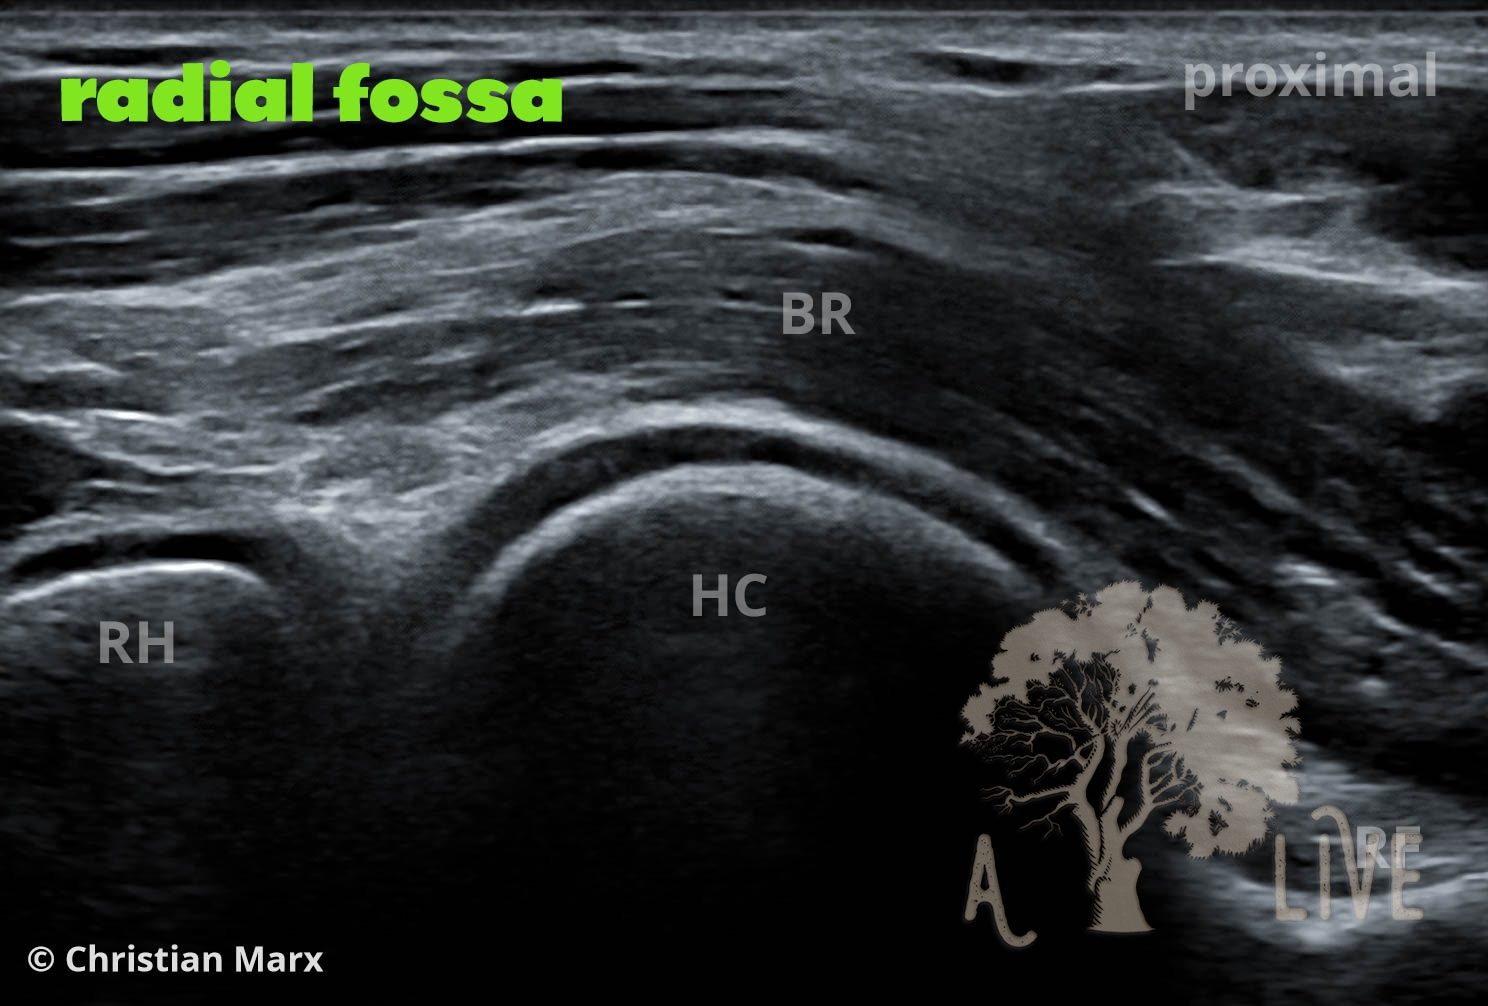

elbow

anterior elbow